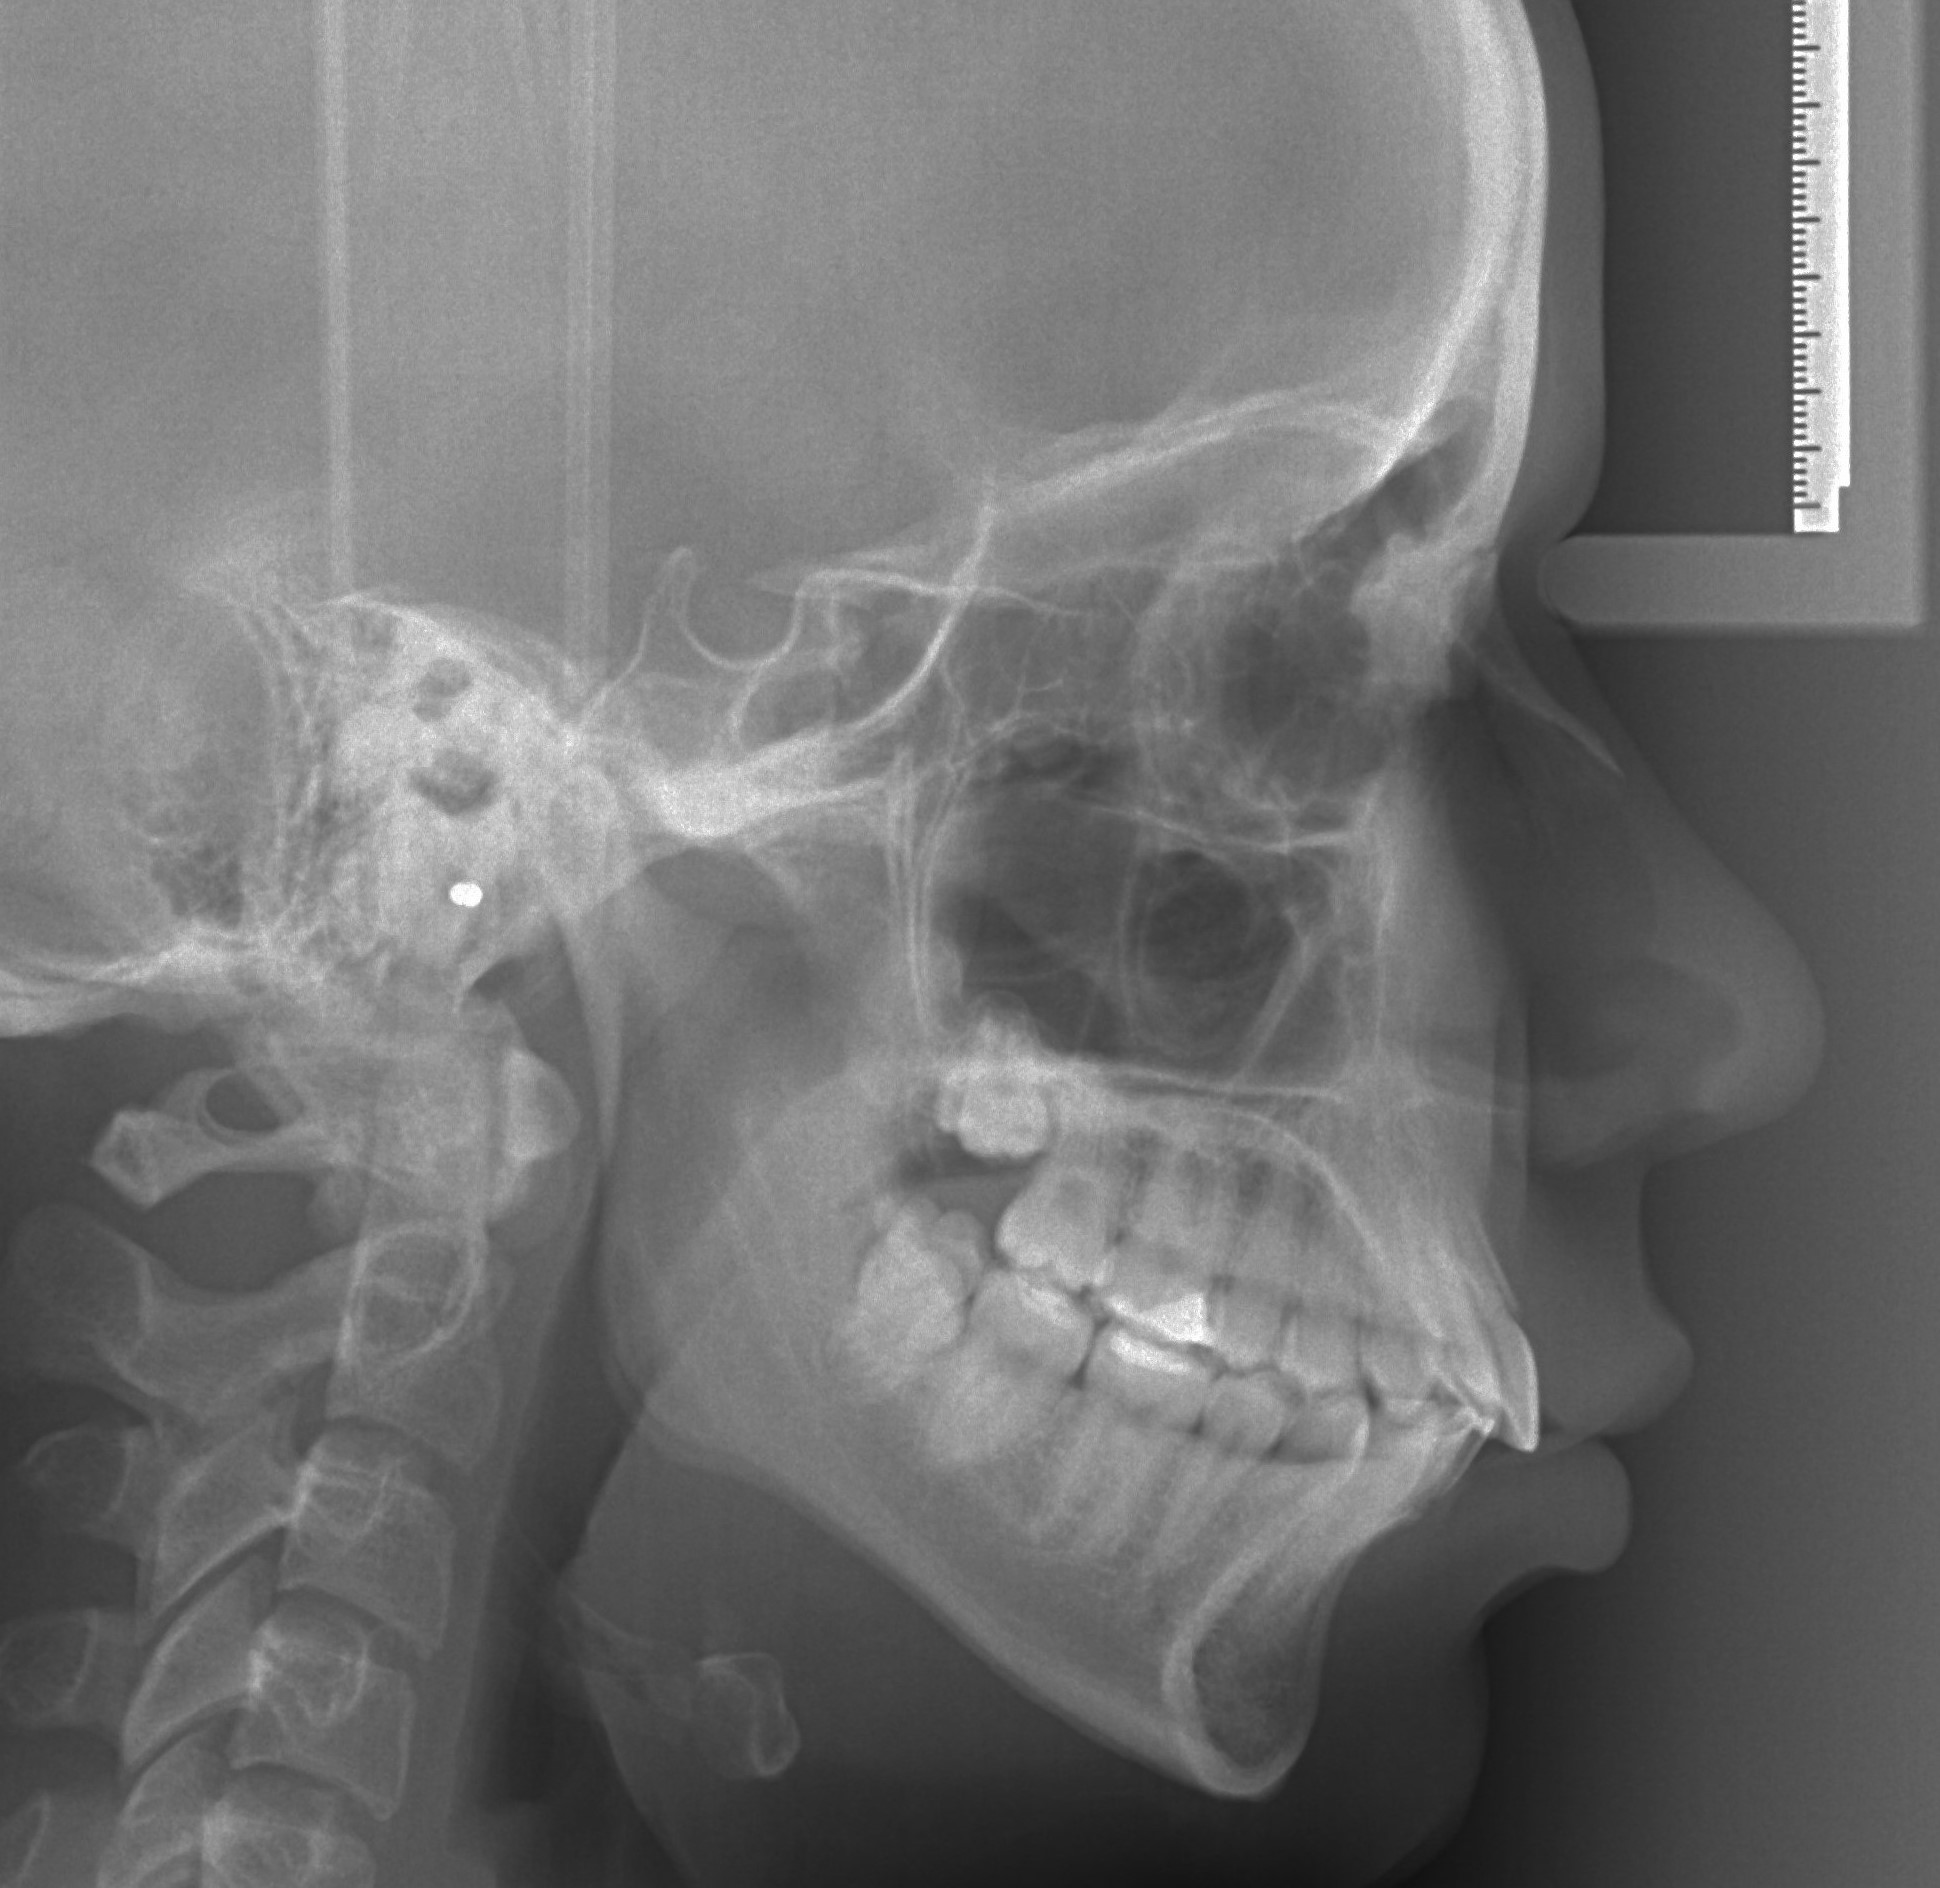

TELERENDGEN PROFILNI SNIMAK GLAVE

Telerendgen se koristi u ortodonciji za analizu odnosa zuba, vilica i lobanje. Na osnovu ovog snimka ortodont planira terapiju i prati razvoj vilica.